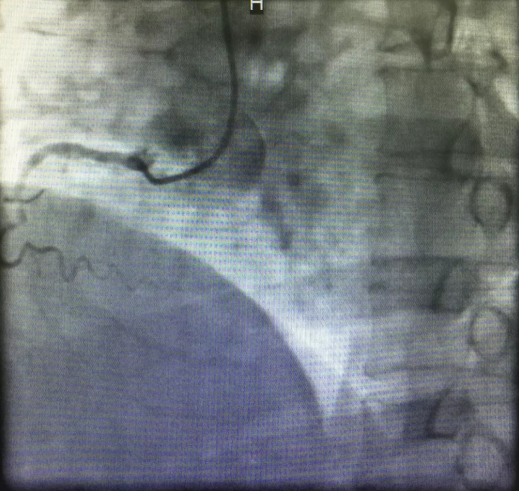

心内三完成男同视频 首例逆向开通冠脉CTO病变